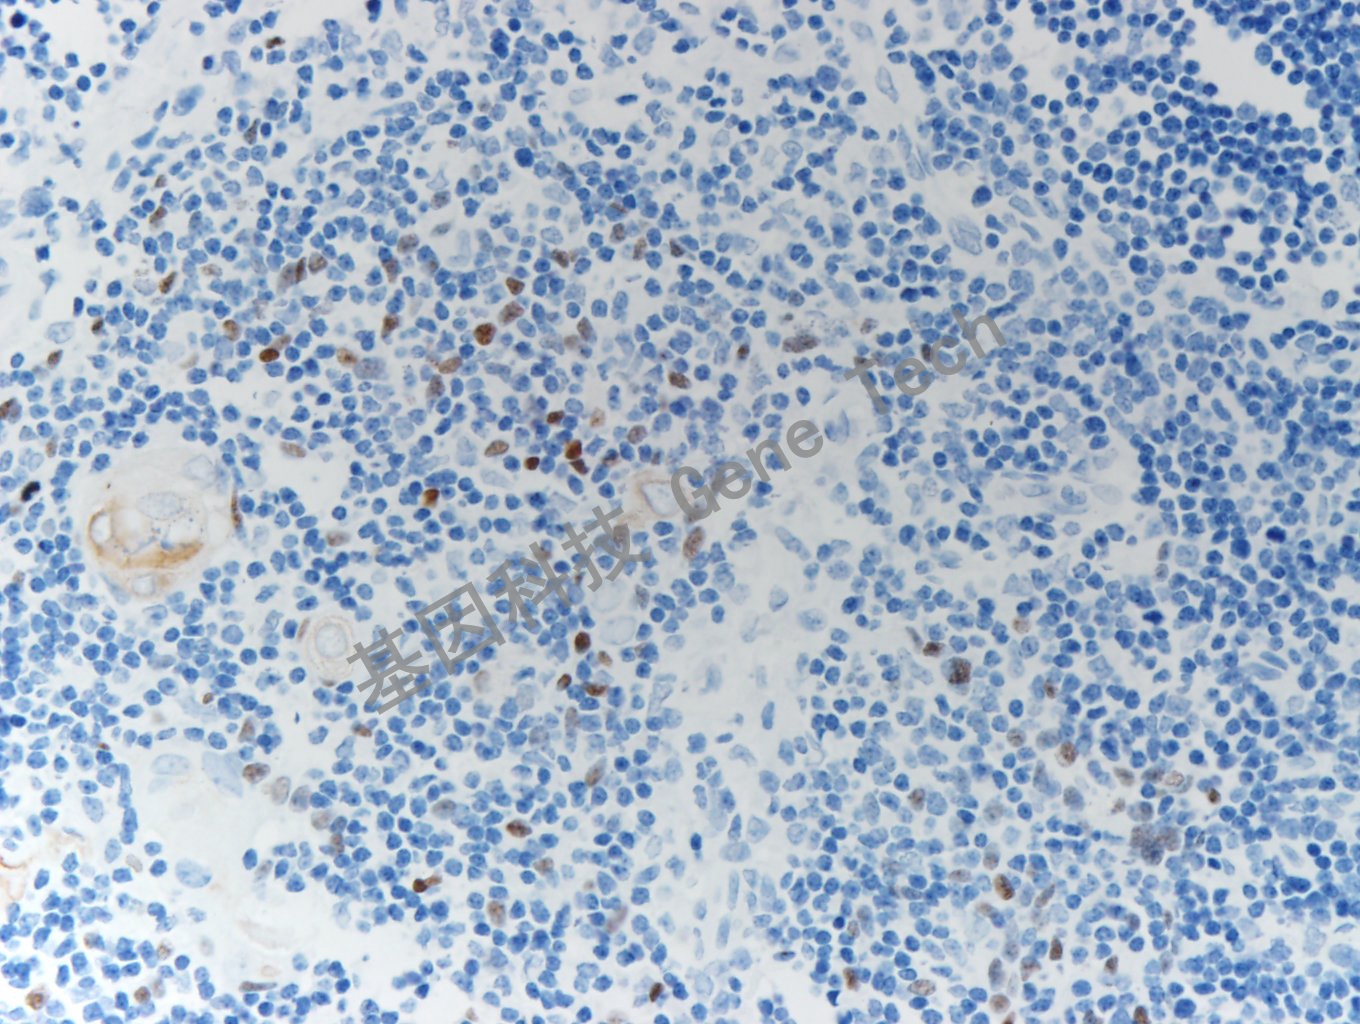

| 簡介:MASH1(Mammalian achaete-scute homologue-1)屬于堿性螺旋環(huán)螺旋家族,是神經(jīng)內(nèi)分泌細(xì)胞分化的關(guān)鍵轉(zhuǎn)錄因子,有助于區(qū)分類癌和高級別神經(jīng)內(nèi)分泌癌。MASH1在小腦、正常甲狀腺C細(xì)胞和胸腺上皮細(xì)胞等正常組織中有表達(dá),在腦癌、胸腺癌、髓樣癌,如膠質(zhì)瘤、室管膜瘤、甲狀腺髓樣癌等腫瘤組織中表達(dá)。 | ||

| 胸腺石蠟切片,用 MASH1(GT2414)染色,細(xì)胞核陽性,DAB 顯色。 | ||